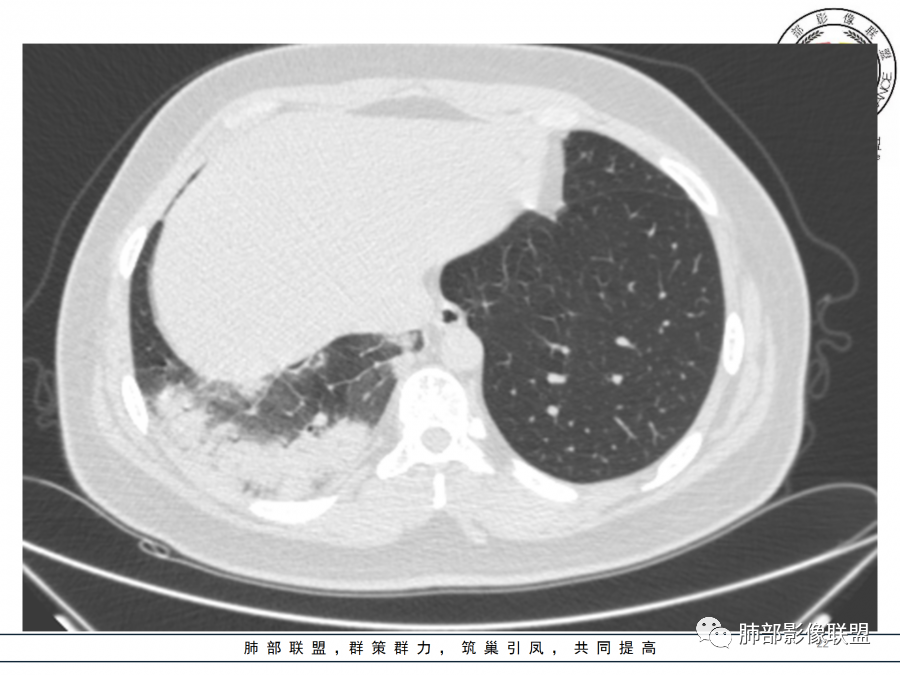

右肺胸膜下实变,病变跨多个叶生长,宽基底与胸膜相连,近端支气管穿行病灶内,并可见片状磨玻璃影,边界清,部分远端小支气管堵塞,支气管略有扩张,周围散发小结节,临床年轻女性,炎性指标高,发热六日,首先考虑感染性病变(肺链,奴卡,隐球,OP)鉴别淋巴瘤。

年轻女性,无明显诱因发热,体温略高,起病较急,有畏寒,右下肺紧贴胸膜下片状实变影,部分融合,外围有结节影,性质比较单一,类似于蘑菇兄弟,病灶周围伴有晕,支气管进入近端扩张远端堵塞,常规考虑感染,肺炎链球菌、隐球菌。

青年女性,发热咳嗽5天,炎症标志物升高。右肺下叶大片实变伴周围GGO,GGO内未见细网格,主体与胸膜平行,似多个病灶融合,实变区内见支气管部分进入,部分支气管受压狭窄,周围可见多发卫星病灶。支持炎性,考虑隐球感染,鉴别op。

年轻女性,急性起病,咳嗽,发热,黄痰,白细胞高,CRP基本正常,基础体健。CT提示右肺下叶实变,宽基底与胸膜相连,长轴平行于胸膜,可见支气管充气征,于病变中央截断,走形自然,胸膜下脂肪间隙可见,倾向于隐球菌,鉴别肺链,军团菌等。

年轻患者,右肺下叶大片状实变影,长轴与胸膜平行,内见含气支气管征,周围磨玻璃晕影。考虑感染性病变,隐球?

病灶长轴与胸膜平行,边缘有晕,病灶融合趋势,支气管进入,走行自如,考虑隐球菌肺炎。

年轻女性,急性发病,咳嗽咳痰五天,炎性指标升高,右肺下叶胸膜下大片实变影,周围见磨玻璃影,边界清晰,长轴与胸膜平行,呈融合趋势,支气管进入走行自然,远端截断,考虑炎性,隐球菌可能。

年轻女性,发热,急性发病,白细胞高,右肺下叶大片实变,长轴与胸膜平行,内见支气管走行,远端截断,周围有晕,晕边界清,考虑感染,隐球可能,鉴别淋巴瘤。

年轻女性,右肺下叶胸膜下多发实变、结节影,宽基底与胸膜相连,边缘模糊不清,实变内见支气管穿行,血象高,考虑感染性病变,大叶性肺炎?隐球?

青年女性,发热咳嗽急性起病,右肺下叶大片状实变密度影,长轴平行于胸膜,边缘模糊可见磨玻璃影及高密度结节影,实变内可见支气管穿行,直达病灶远端,考虑感染性病变,隐球菌可能大。

右肺胸膜下实变,病变跨多个叶生长,相互融合,宽基底与胸膜相连,支气管气象,并可见片状磨玻璃影,边界清,炎性指标高,发热六日,考虑感染病变,链球菌?腺病毒待排。

右肺下叶大片状实变影,长轴平行于胸膜,边缘模糊可见磨玻璃影,支气管进入,部分近端阻塞,考虑感染性病变,隐球菌,鉴别大叶性肺炎。

年轻女性,起病急,白细胞,C反高,存在感染。右下肺大片实变影,支气管充气征,长轴平行胸膜,似多个病灶融合,周围GGO,部分清,部分不清。考虑感染,隐球可能。

青年人,右肺多发团片状阴影,边缘模糊,周围可见磨玻璃影,内部有支气管空气征,考虑感染性病变,隐球菌感染可能。

右肺下叶大片状实变影,从外向内,长轴平行于胸膜,边缘模糊,可见磨玻璃影,支气管进入,远端部分阻塞,考虑感染性病变,隐球菌,鉴别淋巴瘤。

26岁,女性,发热、咳嗽5天。咳少量黄痰,起病急,病程短,白细胞及中性高,血沉及D-二聚体增高。胸部CT:右肺下叶大片实变,长轴沿胸膜分布,宽基底与胸膜接触,边界不清,周围GGO,部分团片影融合,病灶内可见支气管充气征,部分支气管进入病灶后阻塞。考虑:感染性病变,隐球菌?脓毒肺栓塞?鉴别:肺炎型肺Ca。

年轻女性,右肺下叶一大片实变影,似有多个结节影融合,周围有晕,内见支气管充气征,部分支气管进入后截断,病变近胸膜,长轴胸膜平行,考虑炎性,隐球菌首先考虑。

青年女性,影像表现右肺下叶胸膜下大片状实变影,近端见充气支气管征,边缘见片状磨玻璃影,下叶背段尚可见一结节。考虑感染性病变,隐球菌感染可能。

右下肺大片实变影,空气支气管征,边缘GGO,小叶间隔增厚,周围有蘑菇兄弟,基底宽,与胸膜平行,考虑隐球菌感染,鉴别肺炎型肺癌。

晨读:年轻女性,右肺胸膜下实变影,平行于胸膜,边缘磨玻璃影,内见支气管充气征,走形自然,略扩张。考虑感染性改变,隐球,肺链。2月发病,病毒性肺炎要考虑。鉴别淋巴瘤。

晨读:年轻女性,发热咳嗽5天。白细胞计数升高。右肺下叶大片状高密度影,边缘模糊,有实变 GGO,其内见支气管气相、无受压变细,无枯枝表现,其近端支气管无异常,右肺下叶背段见结节状影,定性考虑:炎症,隐球菌感染可能,炎症型肺癌不支持。

右下肺胸膜下大片状高密度影,其长轴与胸膜平行,病灶近端GGO模糊,部分支气管进入后阻断,支持感染性病变,考虑隐球菌